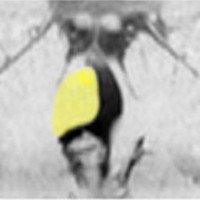

第4室床過誤腫の典型例です

新生児期より動作停止と右眼瞼のちく搦,4ヶ月で右眼の閉眼と口角の引きつれ(顔面けいれん)が目立つようになりました。2歳時には数十秒ごとに発作を繰り返していました。

MRIでは橋の背側(第4脳室床)にT1/T2で等信号の隆起(腫瘤)がみられました。